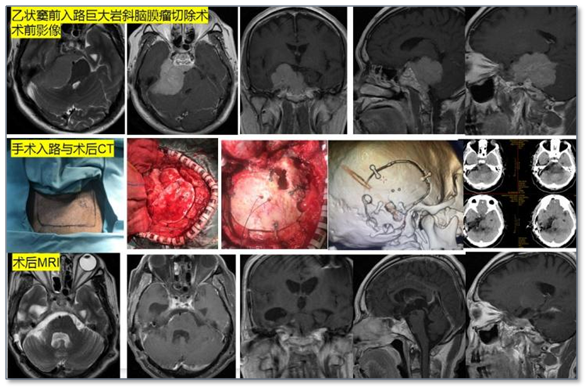

神经外科在梁日初主任的带领下发展迅速,2020年通过湖南省首批临床重点专科验收,2023年获批国家级临床重点(培育)专科。目前科室诊疗范围几乎涵盖所有神经外科疾病领域。设有脑脊髓血血管、颅内肿瘤、功能神经外科、颅脑创伤及神经重症四个拥有区域优势的亚专业。在湘南地区最早开展巨大动静脉畸形的复合手术切除、神经内镜下垂体瘤切除、植物人促醒手术、神经外科机器人手术、脑深部电刺激术、唤醒麻醉下功能区肿瘤切除术等。

目前脑血管外科亚专业组的诊治水平在全国与全省都处于领先地位,湖南省首家开展锁孔入路动脉瘤夹闭术,能常规开展几乎所有复杂疑难脑血管疾病手术,如多模态监测下开展颅内复杂动脉瘤夹闭术、内镜联合显微镜治疗复杂动脉瘤,杂交手术治疗巨大脑血管畸形等。其中儿童脑动静脉畸形破裂急性期的一期切除术,技术处于全国领先地位,曾经在全国开展多次学术交流活动。